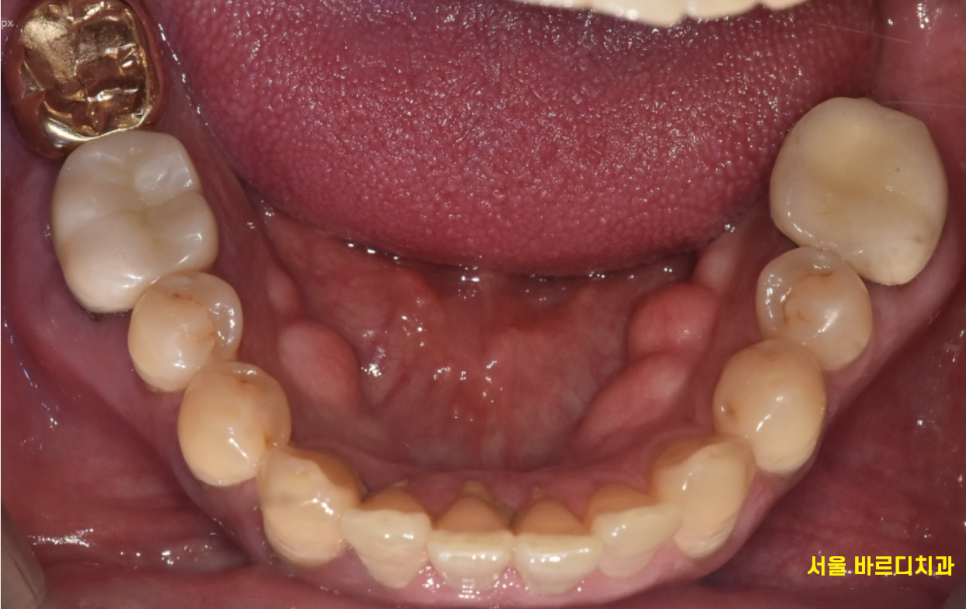

암사역 치과를 방문해주신 한 환자분 사진인데

겉으로는 멀쩡해 보이지 않나요?

피가 나는 부분도 없고

검은 점도 없어보이고 말이죠,,?